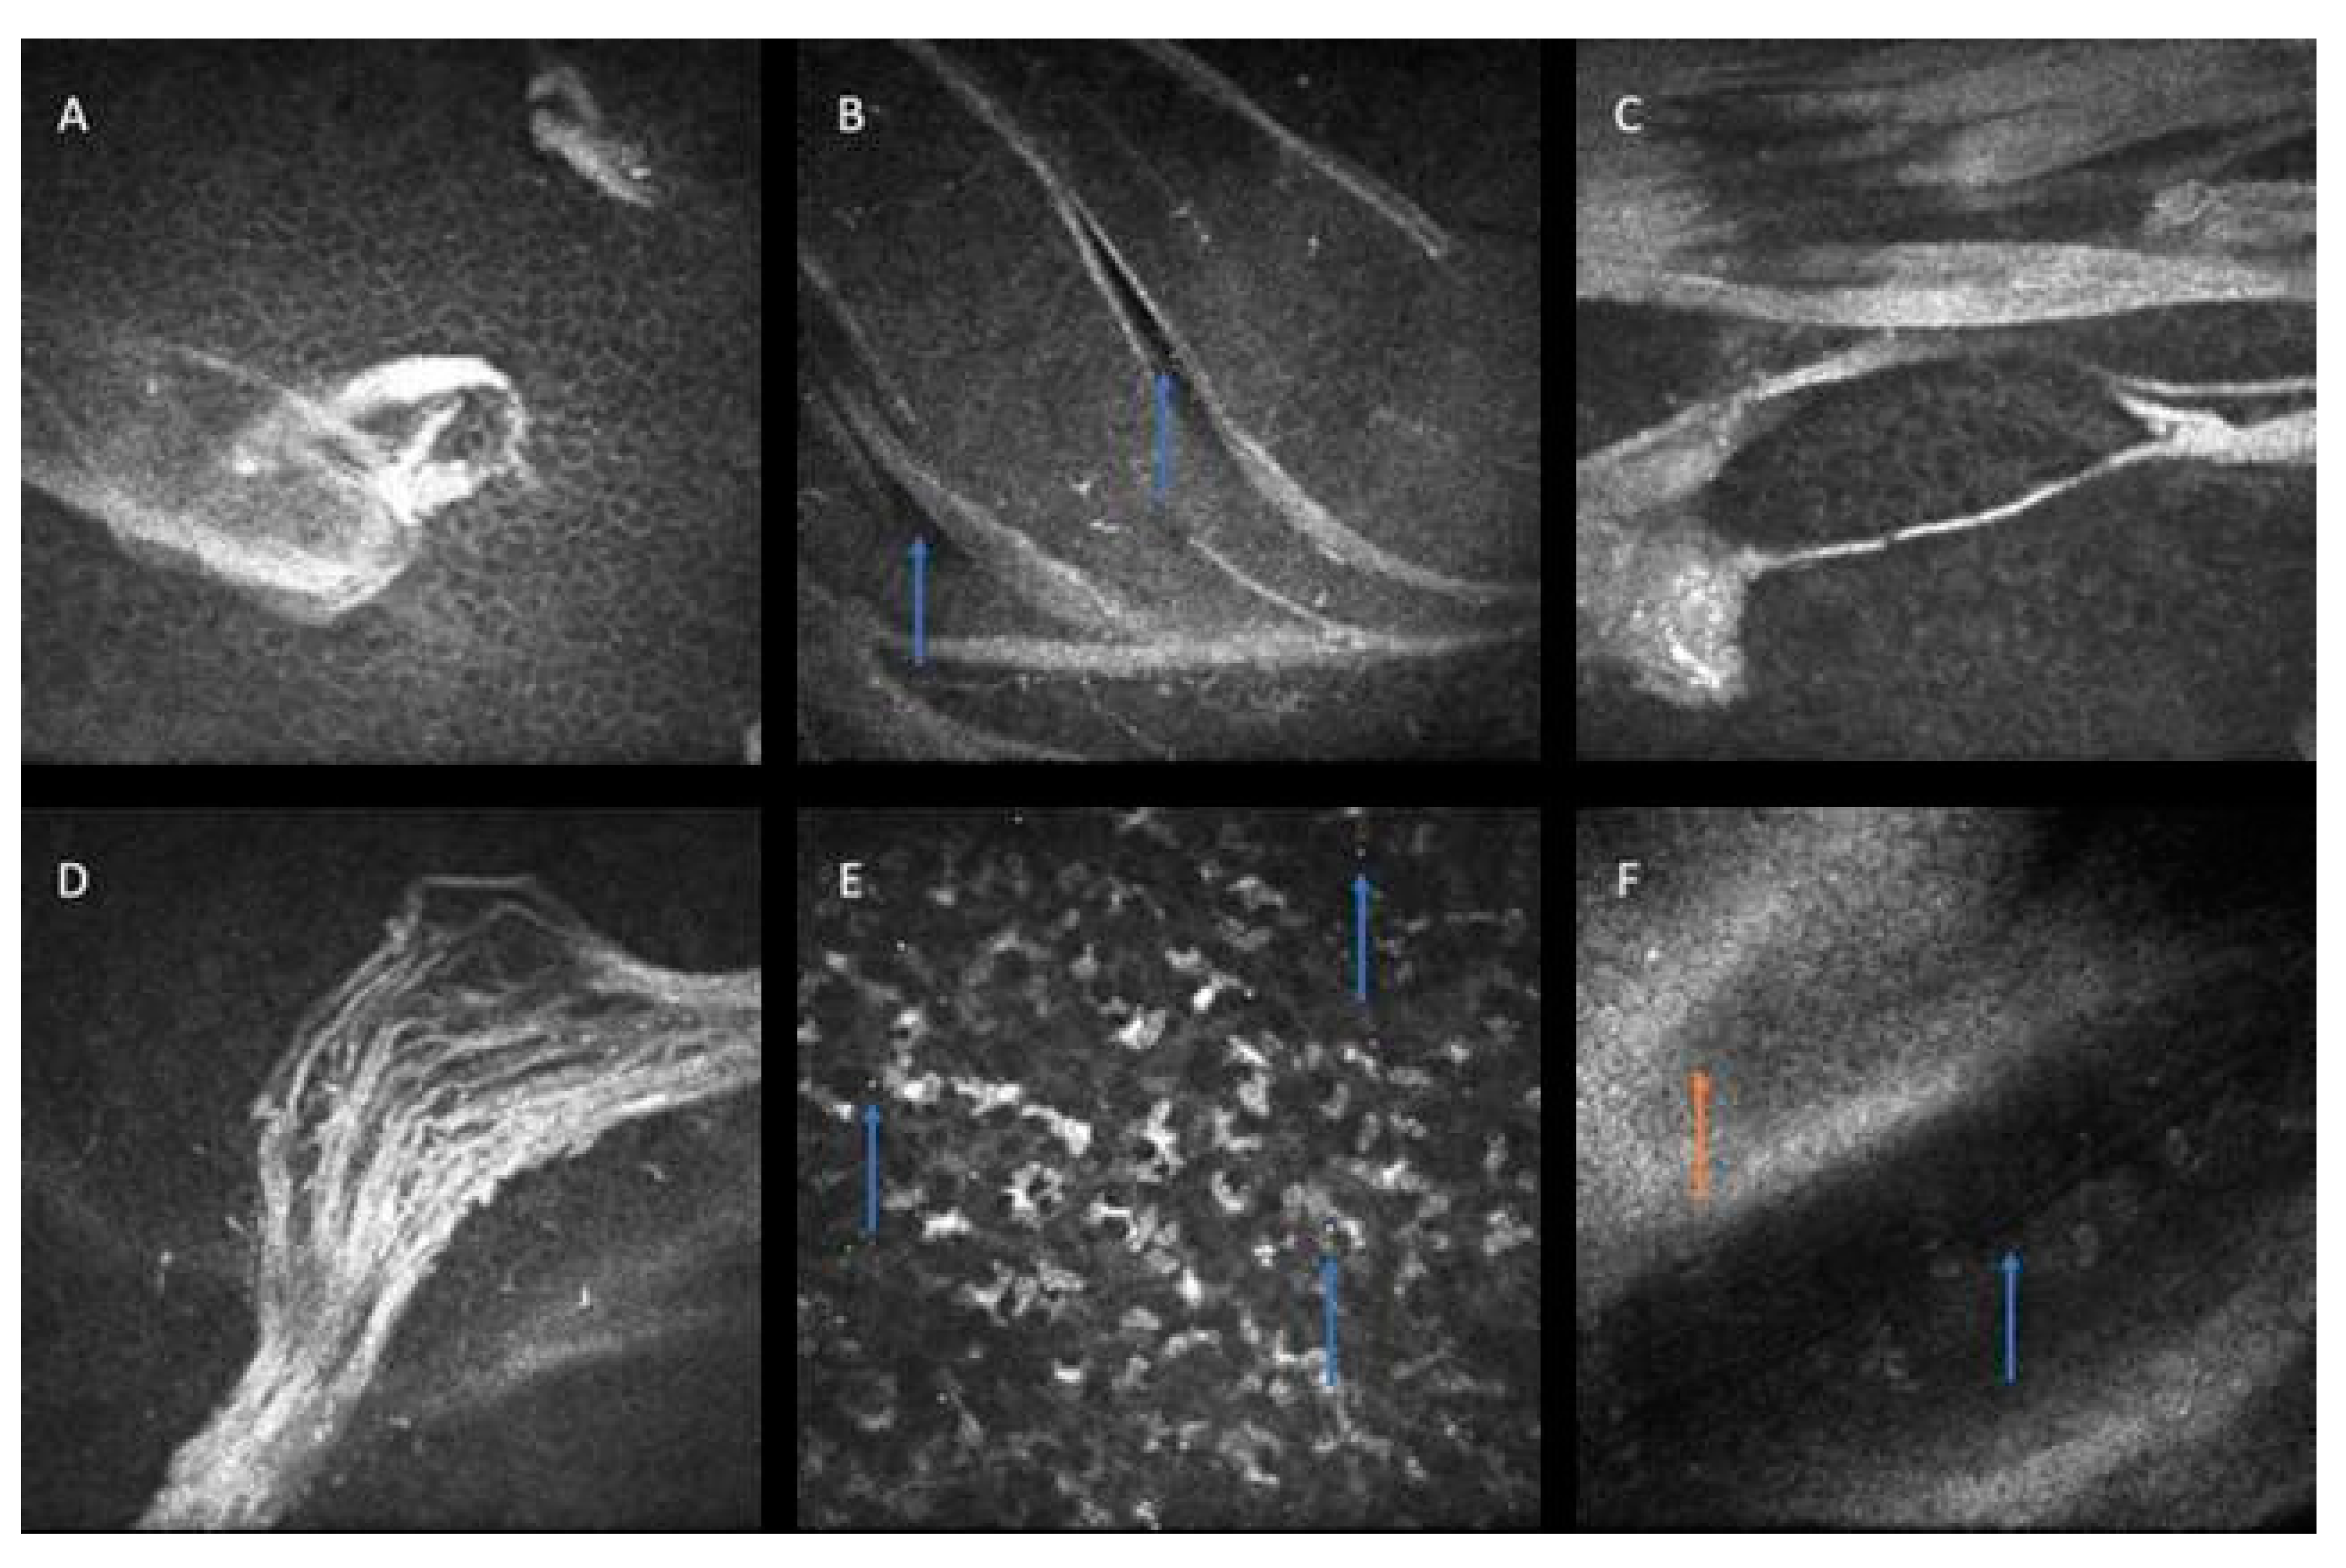

- Hernández-Quintela, E.; Mayer, F.; Dighiero, P.; Briat, B.; Savoldelli, M.; Legeais, J.-M.; Renard, G. Confocal microscopy of cystic disorders of the corneal epithelium. Ophthalmology 1998, 105, 631–636. [Google Scholar] [CrossRef]

- Rosenberg, M.E.; Tervo, T.M.; Petroll, W.M.; Vesaluoma, M.H. In vivo confocal microscopy of patients with corneal recurrent erosion syndrome or epithelial basement membrane dystrophy. Ophthalmology 2000, 107, 565–573. [Google Scholar] [CrossRef] [PubMed]

- Kobayashi, A.; Yokogawa, H.; Sugiyama, K. In vivo laser confocal microscopy findings in patients with map-dot-fingerprint (epithelial basement membrane) dystrophy. Clin. Ophthalmol. 2012, 6, 1187–1190. [Google Scholar] [CrossRef] [PubMed][Green Version]